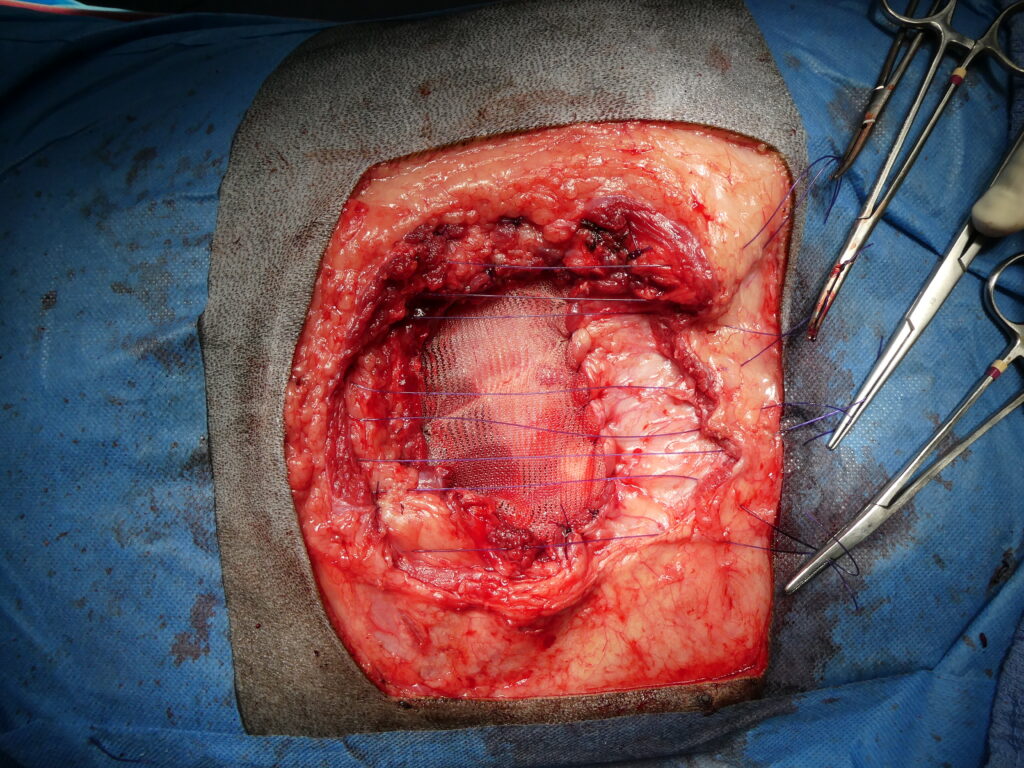

Chirurgie avec résection costale et reconstruction pariétale sur le chien cité ci-dessus.

De gauche à droite et de haut en bas, l’intervention débute par l’exérèse large de la tumeur thoracique, incluant la résection de trois côtes infiltrées afin d’obtenir des marges chirurgicales satisfaisantes. La dissection se poursuit par le retrait complet de la masse tumorale, avec libération soigneuse des adhérences aux tissus adjacents. Une fois la tumeur retirée, un large défect de la paroi thoracique est visible, laissant apparaître le poumon sous-jacent. La reconstruction débute par la mise en place d’un filet de polyéthylène destiné à restaurer la continuité et la rigidité de la paroi thoracique. Le filet est ensuite fixé et suturé, permettant le rapprochement des tissus et la reconstitution d’une paroi thoracique fonctionnelle et stable. Le dernier cliché illustre l’état clinique du chien le lendemain de l’intervention, confortable, mobile, sans douleur apparente, et apte à rentrer à domicile.